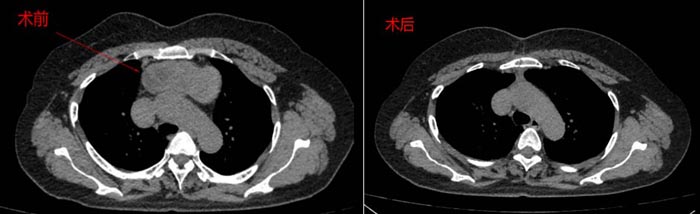

近日,患者刘女士因胸骨后巨大甲状腺肿来我院就诊,术前CT提示胸骨后有超过10公分的巨大甲状腺肿瘤,与胸主动脉、主支气管、无名静脉、心包等重要脏器都紧密粘连,手术稍有不慎,后果不堪设想。我院普外甲状腺病区医生团队接诊后,高度重视,邀请胸外科、麻醉科、重症医学科组成了MDT小组为其进行会诊,专家们为患者进行了详细的病情分析及风险评估,得到家属同意后,一致决定为其行“开放劈胸手术”。患者在各兄弟科室的通力协作下,历经5个小时,手术顺利,术后恢复良好。

患者术前术后影像学对比